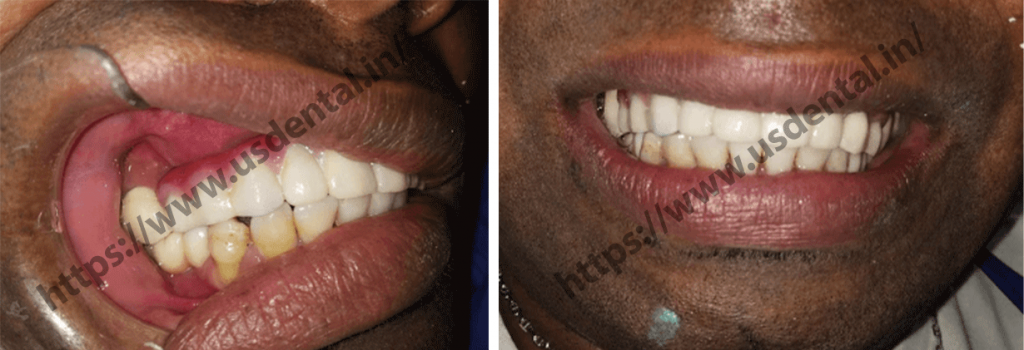

The patient visited US dental all the way from Africa with multiple missing teeth complaint. The patient had a complaint about unpleasing smile and was also unable to chew food properly. Because of the intake of unchewed food, he even started having constipation. On clinical examination, it was observed that the patient was having missing upper and lower anterior teeth.

The patient was extremely happy with the results and very satisfied with his new smile. He was so happy that finally he can chew his food properly without having to miss a bit of his diet. Now, for him, no more compromised piece of food and only complete biting. He said to us, now that he can enjoy his food with his new teeth, he is sacred about his weight gain

The patient was extremely happy with the results and very satisfied with his new smile. He was so happy that finally he can chew his food properly without having to miss a bit of his diet. Now, for him, no more compromised piece of food and only complete biting. He said to us, now that he can enjoy his food with his new teeth, he is sacred about his weight gain

The patient was extremely happy with the results and very satisfied with his new smile. He was so happy that finally he can chew his food properly without having to miss a bit of his diet. Now, for him, no more compromised piece of food and only complete biting. He said to us, now that he can enjoy his food with his new teeth, he is sacred about his weight gain